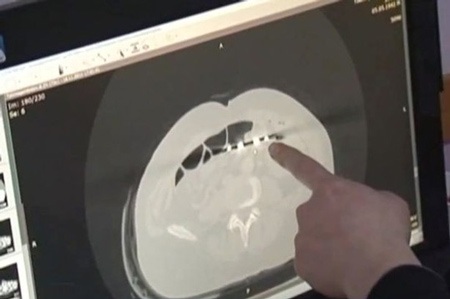

Báo Anh Mirror ngày 14/12 đưa tin ông Karp Ponomaryov, 53 tuổi đến từ Kazakhstan được phẫu thuật cứu mạng hơn 12 năm trước nhưng các nhân viên y tế đã mắc phải lỗi lầm nghiêm trọng: Để lại cây kéo phẫu thuật dài 20 cm trong cơ thể ông. Kể từ đó, người đàn ông này đau dạ dày dữ dội mỗi khi ăn no nhưng ông không bao giờ phàn nàn mà luôn cố gắng vui vẻ vì đã sống sót sau ca phẫu thuật. Tuy nhiên, cách đây 1 tháng, ông mất cảm giác ngon miệng, giảm cân nhanh nên tìm đến bác sĩ để chữa trị.

Bác sĩ Baurzhan Aybaev (44 tuổi) - người kiểm tra kết quả chụp X-quang cho Karp Ponomaryov - cho biết: “Tôi chưa bao giờ thấy bất cứ chuyện gì như thế này. Tôi đã từng thấy miếng gạc phẫu thuật hoặc các thiết bị nhỏ bị bỏ lại nhưng chúng được phát hiện sớm hơn. Có lẽ bệnh nhân đã chịu đau đớn rất nhiều”.